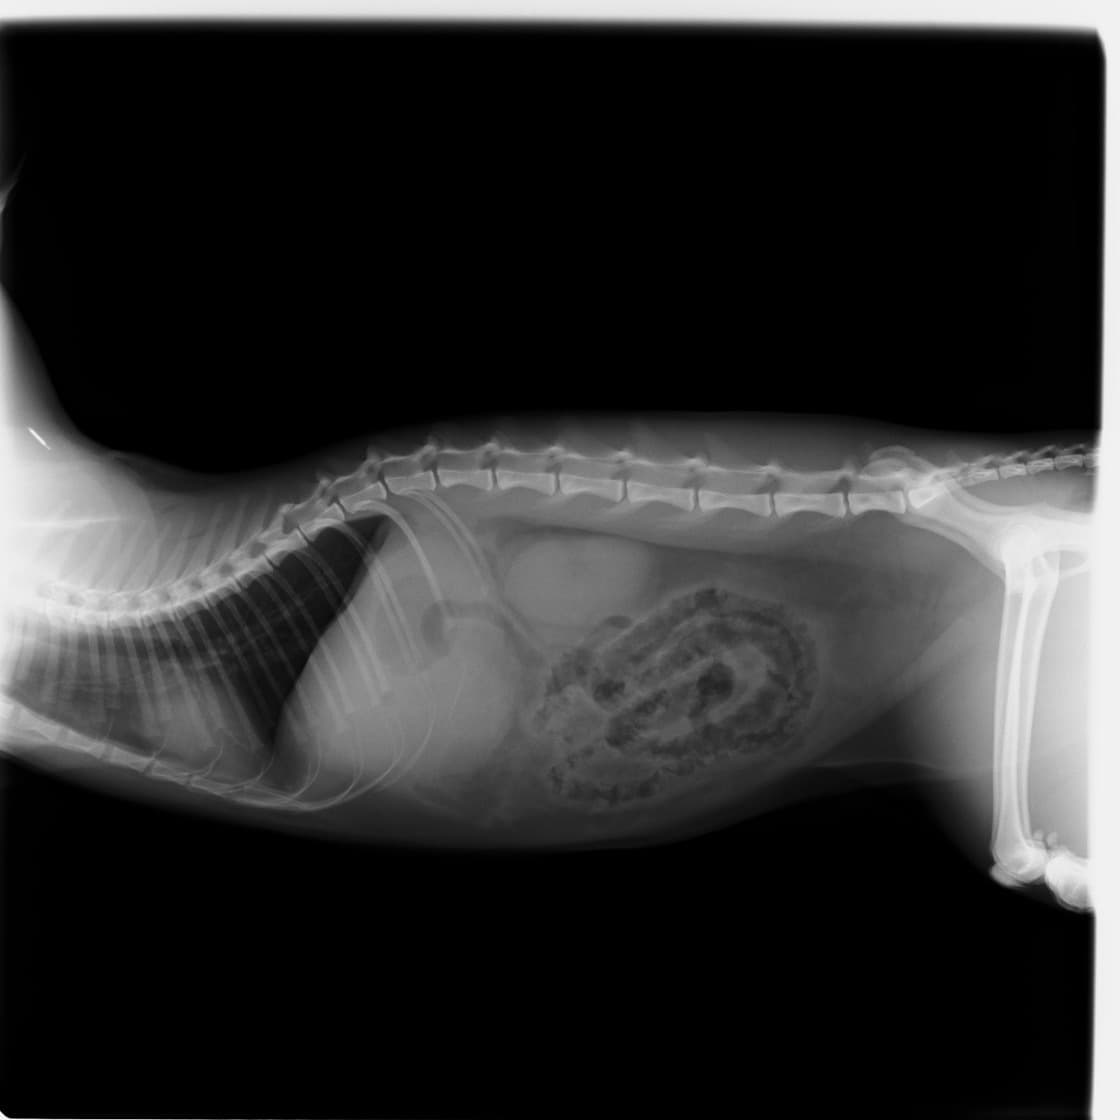

術前のレントゲン

術中写真

左)捻転した胃(右側の赤黒くみられる部分は壊死を起こしています。)

右)腹壁に胃を固定し、再発を防ぎます。

■ 症例:10歳 ドーベルマン 主訴:突然の嘔吐、虚脱